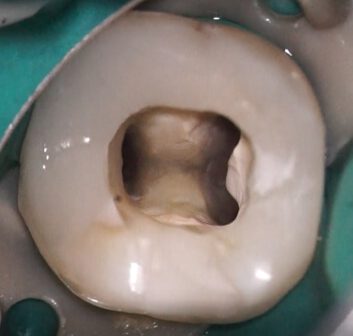

Obturation

The negative pressure obturation technique enables a dense and controlled filling. The image demonstrates how the BC Sealer is actively drawn into all canal areas by the applied vacuum.